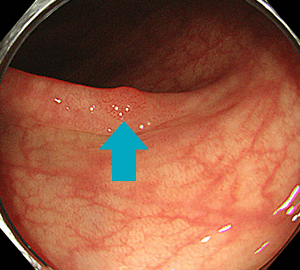

上行結腸に局在する早期大腸がん(左奥は正常な回盲弁)

その病変のNBI観察像です。これを拡大して観察すると…

不整な表面構造と、血管の分布不均一・口径不同・蛇行を認めます。当院は、大腸がん検診(便潜血検査など)で異常が見つかった際の(陽性結果)、二次検診の精密検査としての大腸内視鏡検査(大腸カメラ/下部消化管内視鏡検査)にも対応しております。